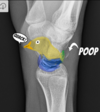

Fratura do platô tibial lateral - Schatzker tipo 2 (traço de fratura + depressão do plato lateral).